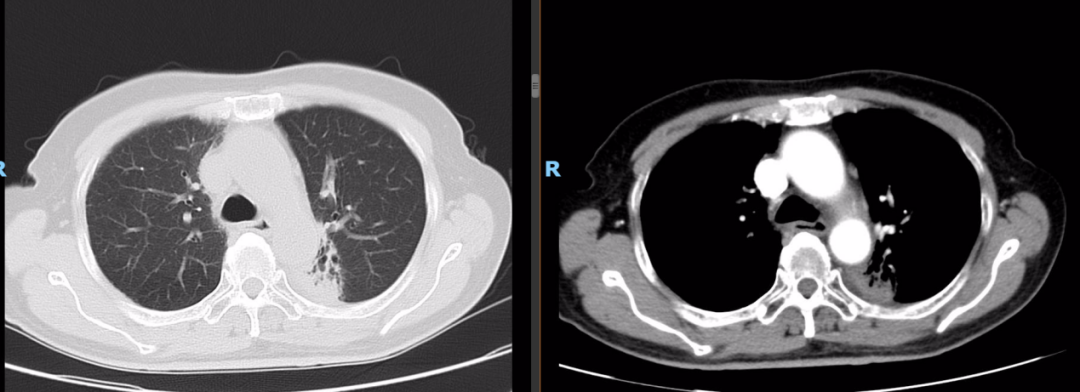

2022-03-28 PET-CT:1、食管癌放化疗后,食管胸中段管壁不规则增厚伴结节状代谢增高,与上次(2021-10-28)PET/CT检查对比,病灶代谢较前明显增高,考虑为肿瘤复发病灶。2、左肺癌放疗后及靶向药治疗后,原左肺上叶团块状高代谢“肿瘤灶”,现范围较前稍缩小,代谢较前稍减低,考虑为治疗后改变(肿瘤完全活性受抑,伴少许炎性反应可能)。

二线治疗

2022年-04-01~2022年08-行化疗+靶向+免疫治疗,具体方案为白蛋白紫杉醇260mg/m2即400mg d1 q3wX6周期;化疗同时行尼妥珠单抗400mg q3w;化疗同期行斯鲁利单抗200mg q3w治疗及维持治疗至今。